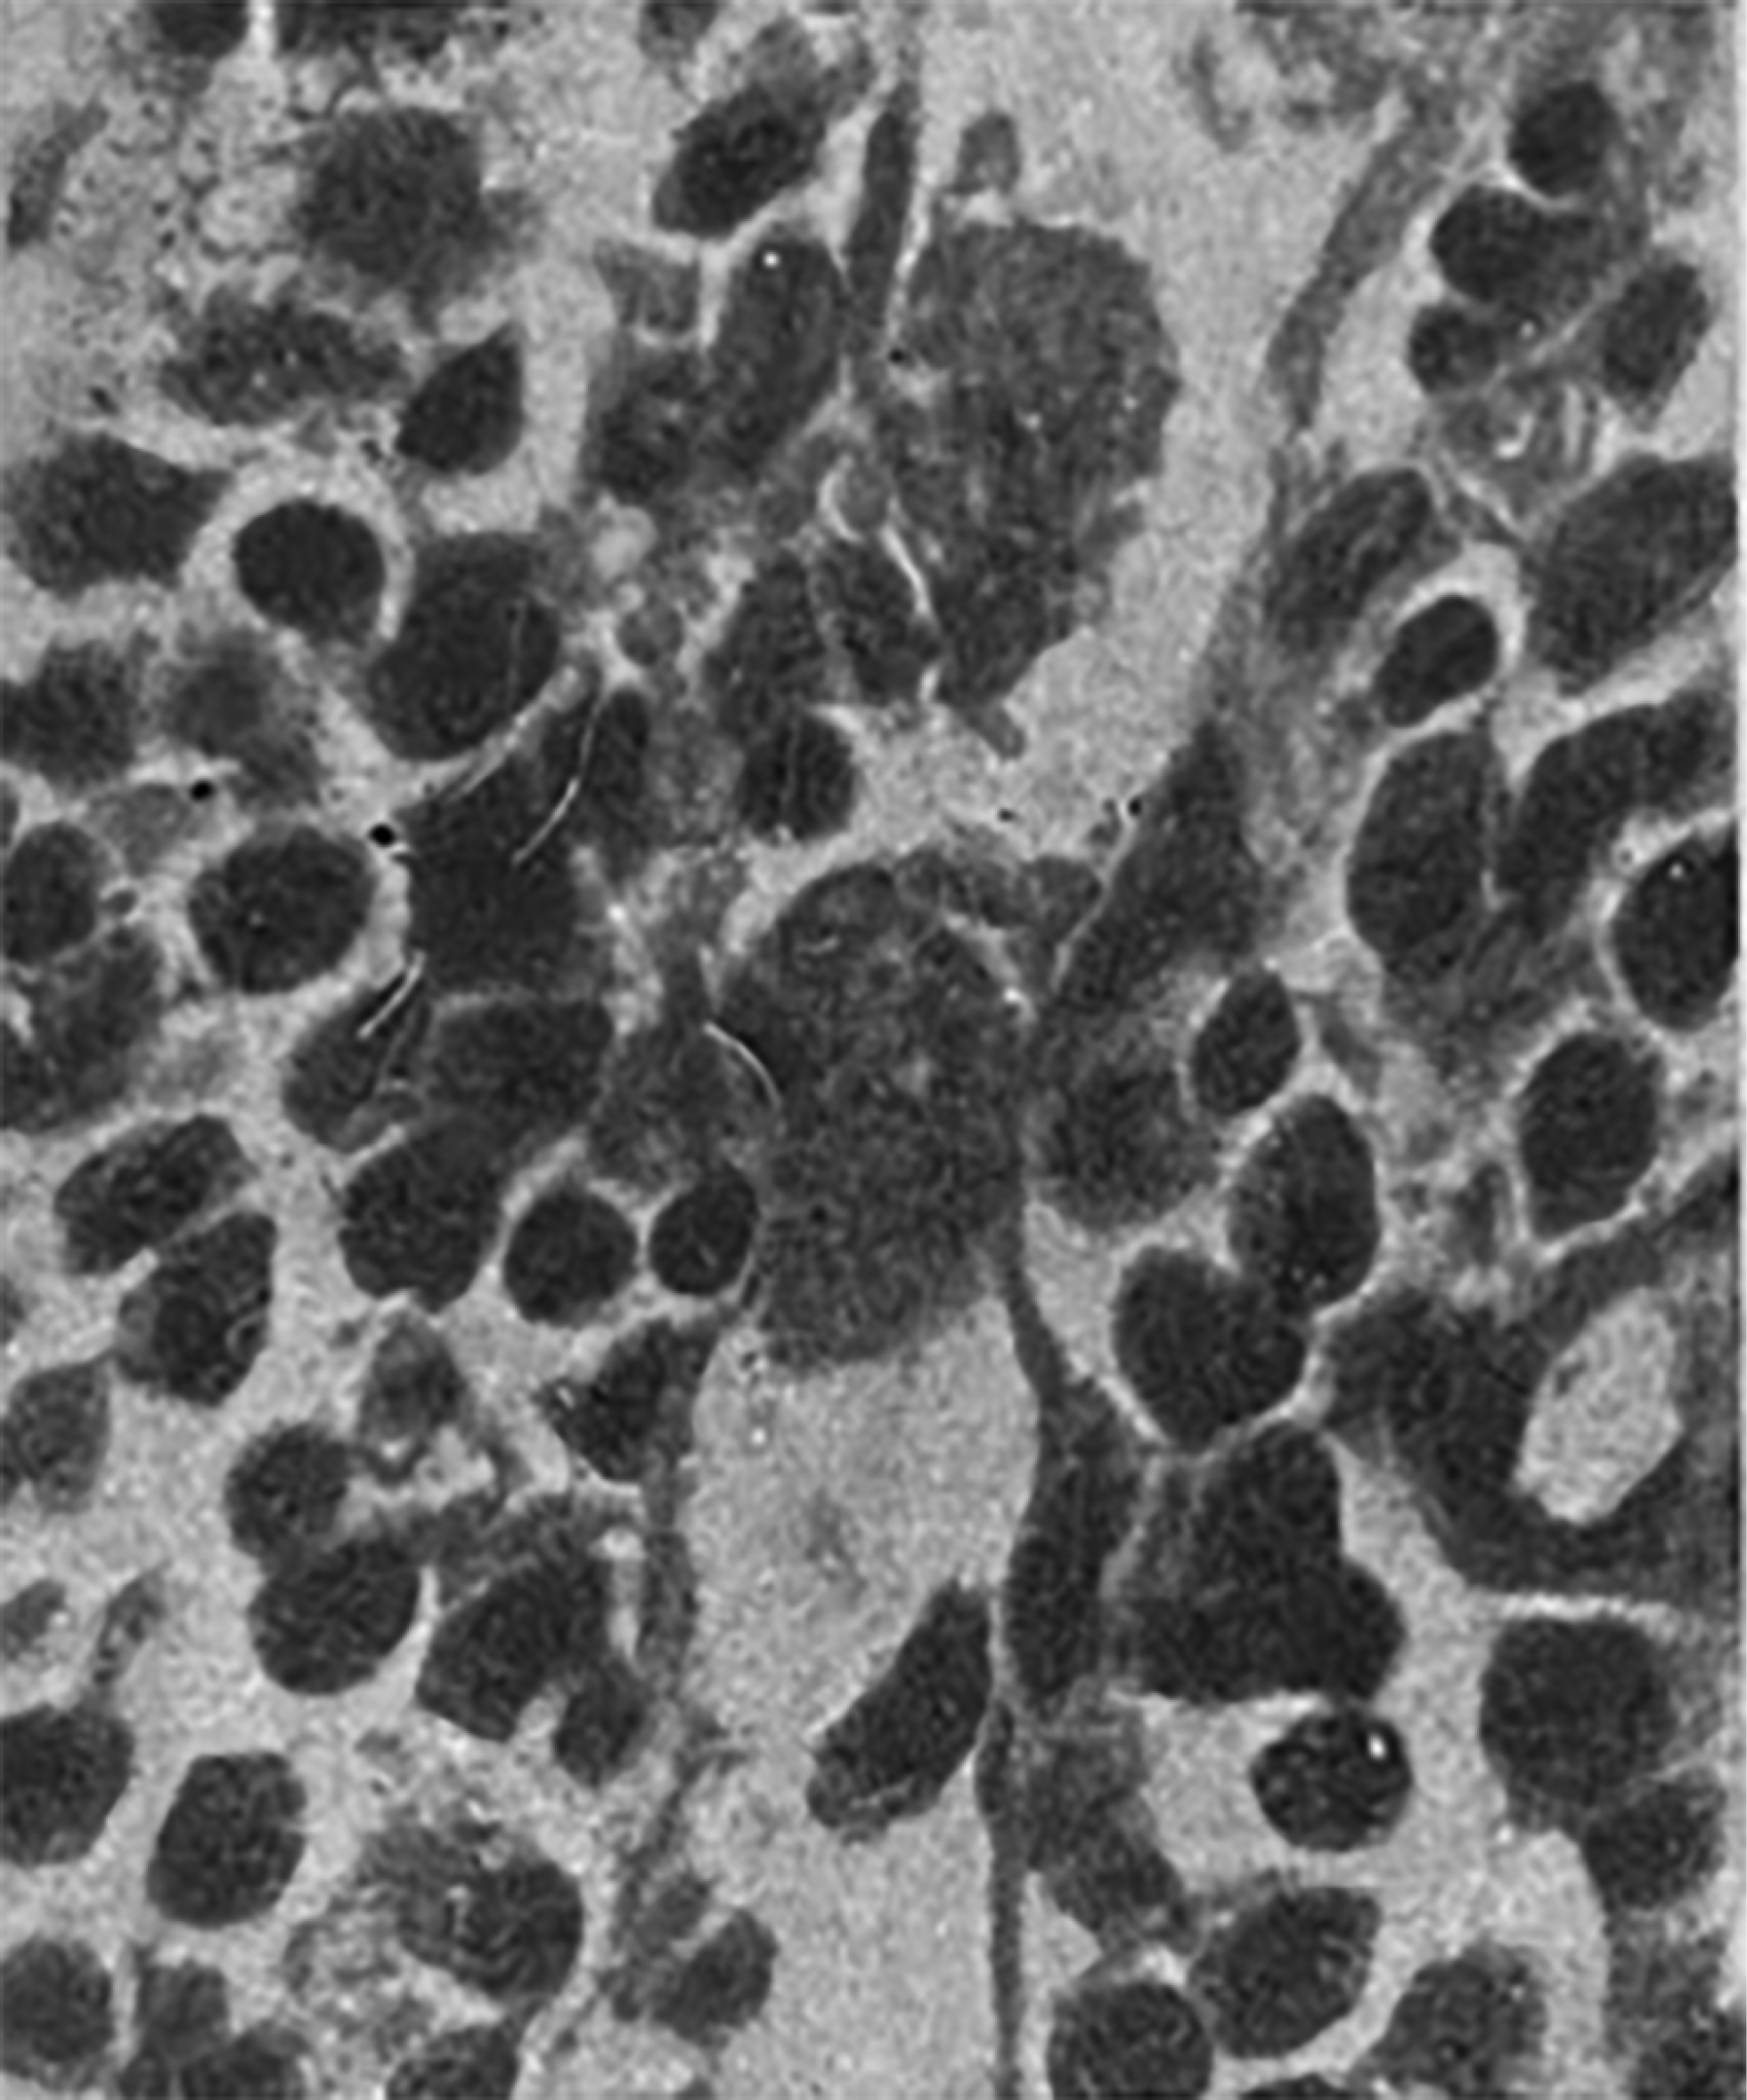

Яков Львович Рапопорт также принимал участие в изучении морфологической реакции ЦНС, гематоэнцефалического барьера на гипоперфузию в ходе операций с использованием аппарата искусственного кровообращения (рис. 5).

Рис. 5. Нейронофагия при острой гипоксии мозга [6].

Fig. 5. Neuronophagia in acute cerebral hypoxia [6].